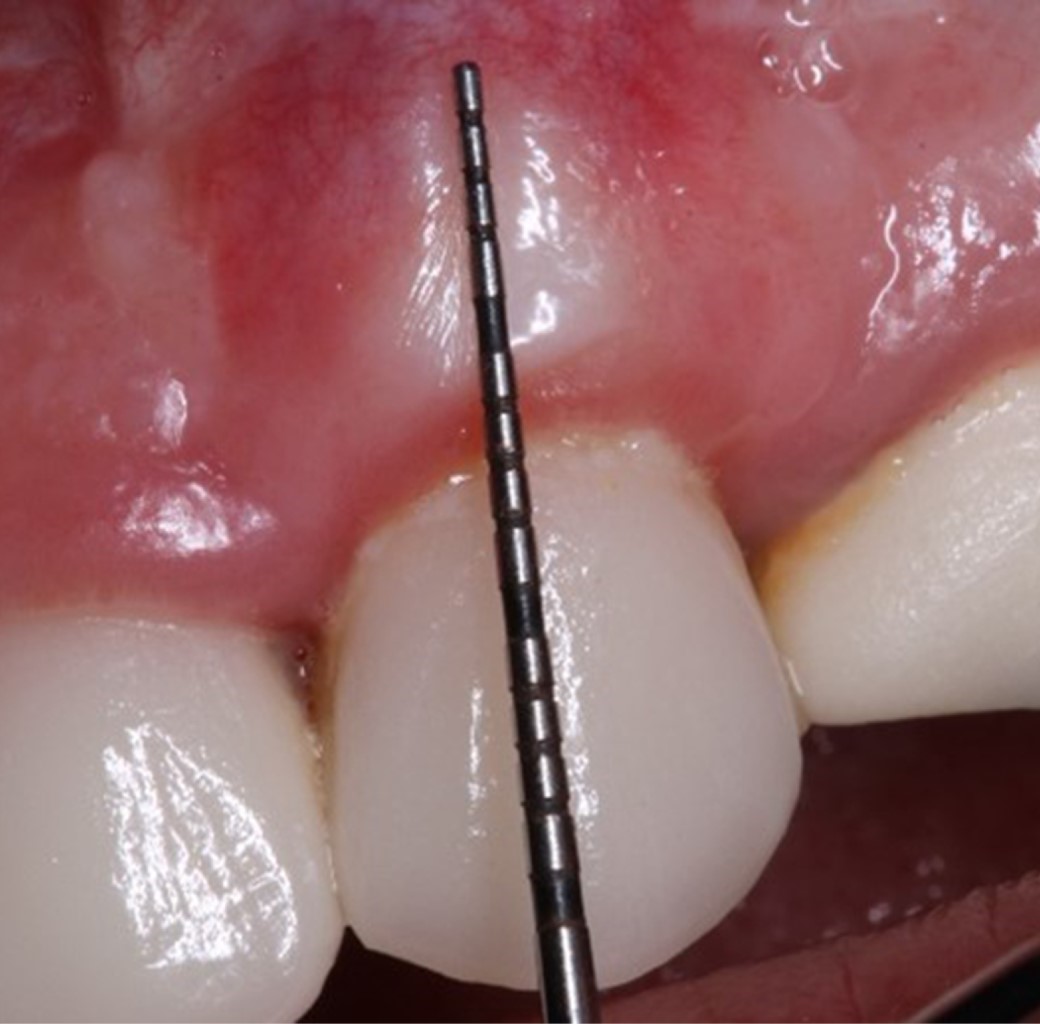

Paciente femenino de 53 años, sistémicamente sana, no fumadora, con alergia referida a penicilinas. Se presenta a consulta dental por inconformidad estética en diente 23 e hipersensibilidad dentinaria, con diagnóstico de recesión gingival (Figura 1).

Clínicamente, se presenta una recesión gingival de 4 mm de longitud en el canino superior izquierdo (diente 23), la cual se formó después de 14 días posteriores a la cementación adhesiva de una carilla de porcelana feldespática; se observa un fenotipo gingival fino, 2 mm de tejido gingival queratinizado, y profundidad al sondeo periodontal no mayor a 2 mm, sin pérdida de inserción interproximal (Figura 2).

Figura 1

Figura 2